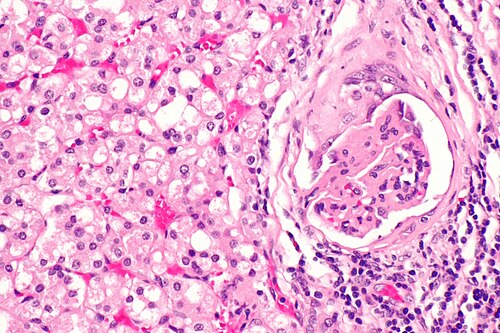

Hybrid tumour of the kidney -- high mag.jpg

Hybrid oncocytic/chromophobe tumour